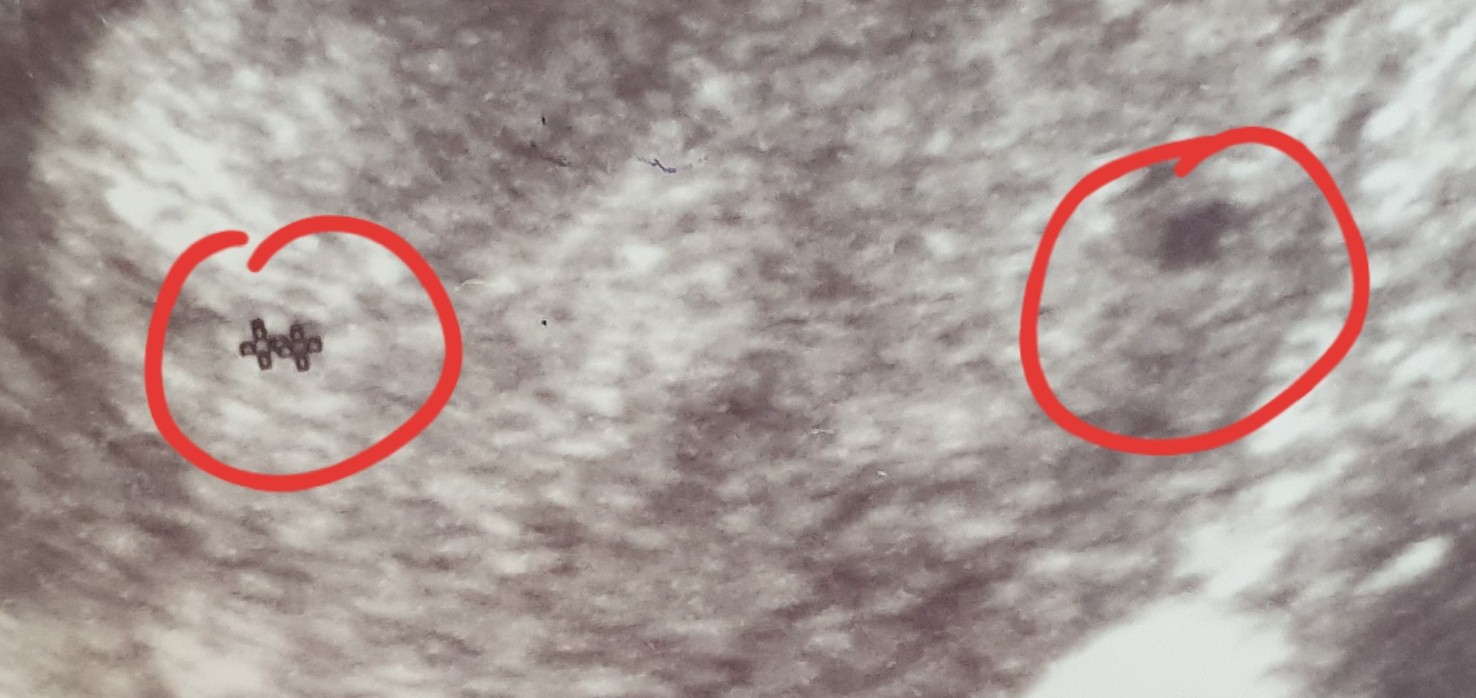

Cześć dziewczyny moj termin pokazuje na 04.01.2022 :) Ale mam pytaniedo Was czy Wy tu widzicie jeden czy dwa pęcherzyki ? pierwsze usg z 5 tygodnia ciazy drugie z 6 tygodnia ciazy. :D Bo już zguplam nic nie wspominal ginekolog o dwóch al3 za to przepisał i duphastpn i luteine A przy pierwszej ciazy pojedynczej tylko luteine.

Niestety nie jestem specjalistą od usg, wiec raczej nie pomogę. Moim zdaniem każdy lekarz by zwrócił uwagę na dwa pecherzyki. Może to jajnik? Dziwne, ze na obu zdjęciach masz mierzony tylko jeden pecherzyk.